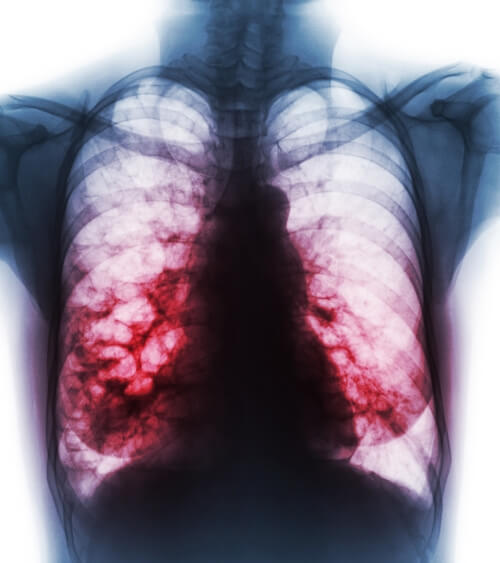

Бронхография при бронхоэктатической болезни.

Бронхоэктазы нижней доли.

Компьютерные томограммы при бронхоэктазах нижней доли левого легкого.